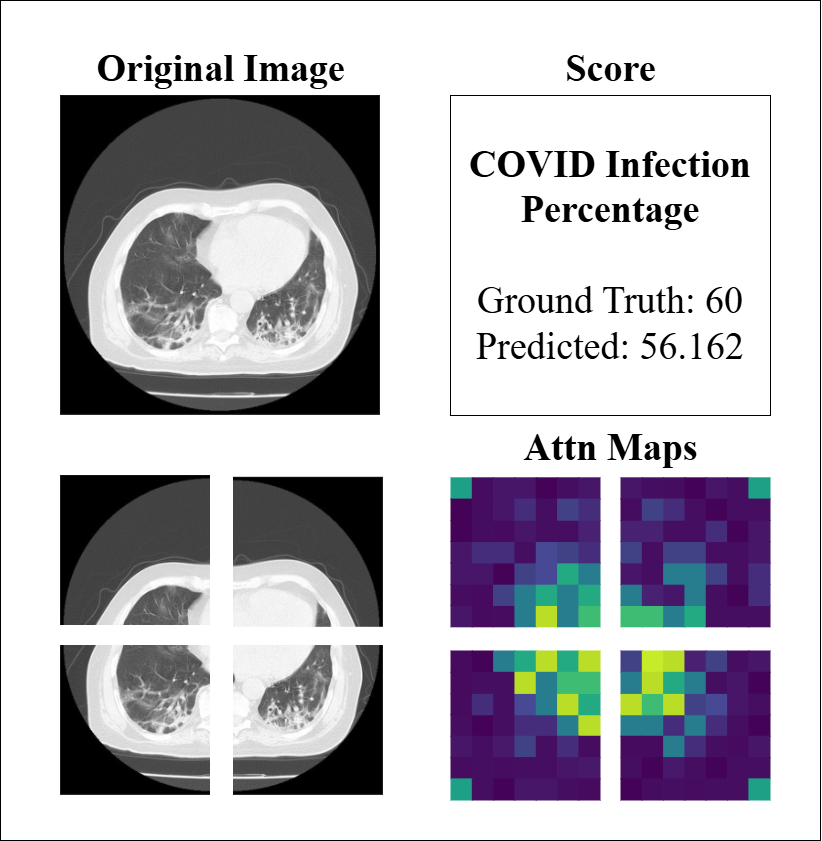

4.4 Model Interpretability

Similarly, to assess the model’s performance on CT imaging, we analyzed attention maps and prediction scores across representative cases, as illustrated in Figure 8. The examples demonstrate the model’s capacity to identify regions of COVID-19 involvement, with attention maps highlighting ground-glass opacities and consolidations that correlate well with infection percentage predictions in most cases (e.g., GT 60 vs. predicted 56.2). The spatial distribution of attention weights aligns with the predicted severity scores, reflecting the model’s ability to quantify disease burden through learned feature importance. However, the third example (GT 22 vs. predicted 6.4) reveals a substantial underestimation, despite attention maps showing patchy activations. This discrepancy may be attributed to CT-specific challenges such as partial volume effects, slice thickness variability, or subtle early-stage findings that complicate severity assessment. These observations emphasize that while the model effectively captures pronounced disease patterns, its performance may be limited by technical factors inherent to CT acquisition and early/mild disease manifestations.